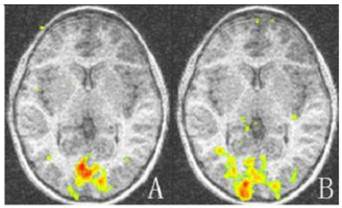

For amblyopic eyes, the activation area of the striate cortex (0.45 ± 0.035) was significantly lower than that of the sound eyes (0.49 ± 0.030, P < 0.05). The activation area of the extrastriate cortex (3.55 ± 0.234) was also significantly lower than that of the fellow eyes (3.77 ± 0.257, P < 0.05; Fig. 1, 3). The cortex activation data are summarized in Table 3. The ID of extrastriate cortex activation had no correlation with that of the striate cortex (R2 = 0.45, P = 0.557), which suggested the striate and ESC deficits are independent and the latter do not arise as a down-stream consequence of the primary visual cortex lesion.

Figure 3

The activation map of the amblyopic and sound eyes relative to baseline for amblyopic children. The activation areas of the amblyopic eyes are much less than that of the sound eyes in striate and extrastriate cortex (P < 0.05). A: Activation map of amblyopic eyes; B: Activation of the sound eyes. Areas with high and low activation are indicated by red and green colors.